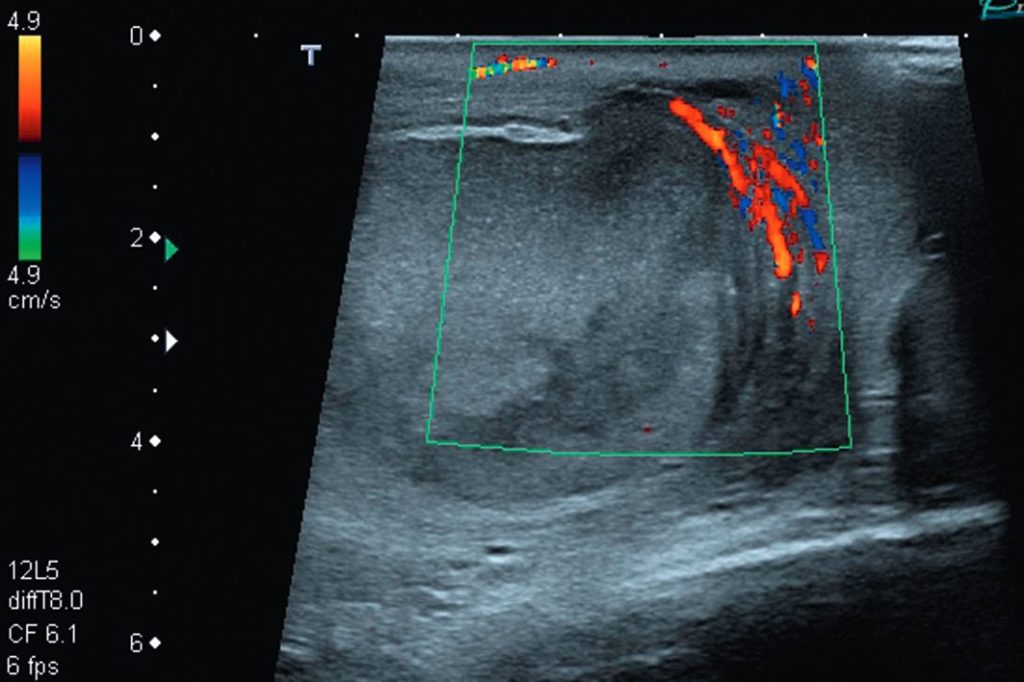

C. En cas de forme vue tardivement, au stade d’ischémie (figure 28.2)

- Testicule et épididyme avasculaires, hétérogènes.

- Hypervascularisation des enveloppes.

Fig. 28.2. Échographie doppler couleur.

Ischémie testiculaire ancienne (une semaine d’évolution) : testicule avasculaire avec hypervascularisation des enveloppes et début de fonte testiculaire.

Source : CERF, CNEBMN, 2022.